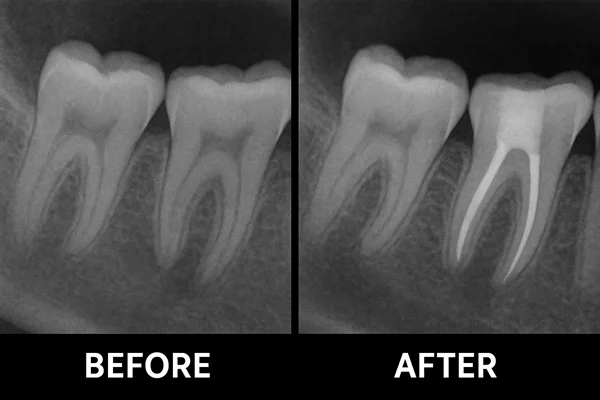

• On the initial visit to the Stoma Advanced Dental Care dental, our endodontist will conduct an X-ray oral examination for your teeth to determine the extent of the infection

• The infected tissue inside the tooth is carefully removed and the canals are cleaned and shaped.

• The cleaned canals are filled and sealed to prevent further infection.